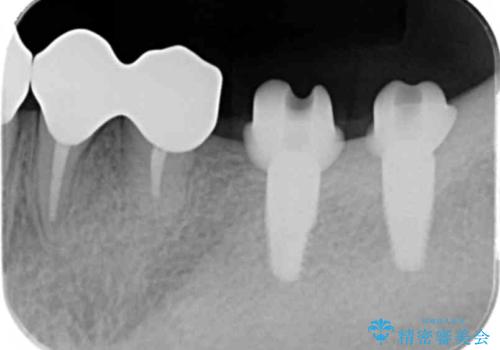

ここの歯の状態を精密に検査し、根管治療、セラミック治療、インプラント治療を含む総合的な歯科治療を計画します。

- 242万円(ジルコニアクラウン・仮歯×7本 インプラント×2本)費用は治療当時の料金となります

部分的な治療ではなく、全体的な治療を任せていただけたことで、清掃性の高く咬合関係の良い治療を行うことができました。